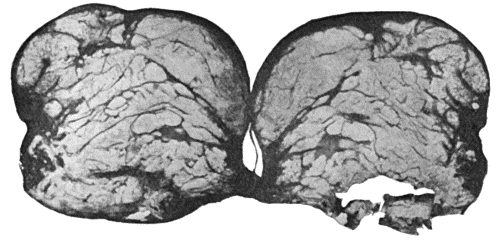

Nerve Tissues.—There is no trustworthy evidence that regeneration of the tissues of the brain or spinal cord in man ever takes place. Any loss of substance is replaced by cicatricial tissue.